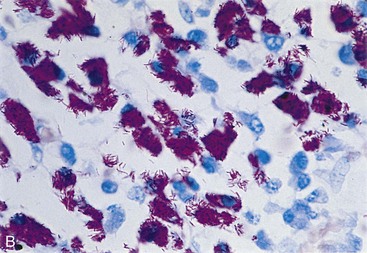

A new spectrum of disease developed in patients with acquired immunodeficiency syndrome (AIDS), making infection with M. avium complex the most common mycobacterial disease in these patients in the United States. In contrast to disease in other groups of patients, MAC infection in patients with AIDS is typically disseminated, with virtually no organ spared (Clinical Case 25-2). The magnitude of these infections is remarkable; the tissues of some patients are literally filled with the mycobacteria (Figure 25-8), and there are hundreds to thousands of bacteria per milliliter of blood. Overwhelming disseminated infections with M. avium are particularly common in patients who are in the terminal stages of their immune disorder, when their CD4 T-lymphocyte counts fall to less than 10 cells/mm3. Fortunately, with more effective antiretroviral therapy and the routine use of prophylactic antibiotics, M. avium disease infections in HIV-infected patients have become much less common. Although some patients with AIDS develop M. avium disease after pulmonary exposure (e.g., infectious aerosols of contaminated water), most infections are believed to develop after ingestion of the bacteria. Person-to-person transmission has not been demonstrated. After exposure to the mycobacteria, replication is initiated in localized lymph nodes followed by systemic spread. The clinical manifestations of disease are not observed until the mass of replicating bacteria impairs normal organ function.

image image

Figure 25-8 Tissue from a patient with acquired immunodeficiency syndrome who is infected with Mycobacterium avium complex, photographed under low (A) and high (B) magnification.